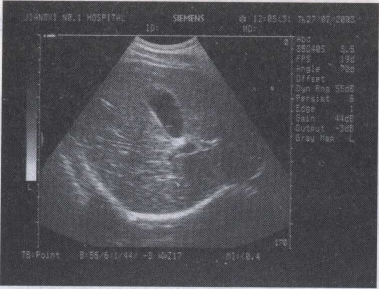

42.女,36岁,上腹疼痛不适2年余。结合超声声像图,诊断为()